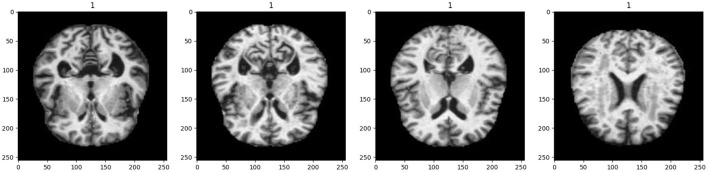

Alzheimer's disease (AD) is a progressive neurological disorder characterized by the gradual deterioration of cognitive functions, leading to dementia and significantly impacting the quality of life for millions of people worldwide. Early and accurate diagnosis is crucial for the effective management and treatment of this debilitating condition. This study introduces a novel framework based on Spectral Graph Convolutional Neural Networks (SGCNN) for diagnosing AD and categorizing multiple diseases through the analysis of functional changes in brain structures captured via magnetic resonance imaging (MRI). To assess the effectiveness of our approach, we systematically analyze structural modifications to the SGCNN model through comprehensive ablation studies. The performance of various Convolutional Neural Networks (CNNs) is also evaluated, including SGCNN variants, Base CNN, Lean CNN, and Deep CNN. We begin with the original SGCNN model, which serves as our baseline and achieves a commendable classification accuracy of 93%. In our investigation, we perform two distinct ablation studies on the SGCNN model to examine how specific structural changes impact its performance. The results reveal that Ablation Model 1 significantly enhances accuracy, achieving an impressive 95%, while Ablation Model 2 maintains the baseline accuracy of 93%. Additionally, the Base CNN model demonstrates strong performance with a classification accuracy of 93%, whereas both the Lean CNN and Deep CNN models achieve 94% accuracy, indicating their competitive capabilities. To validate the models' effectiveness, we utilize multiple evaluation metrics, including accuracy, precision, recall, and F1-score, ensuring a thorough assessment of their performance. Our findings underscore that Ablation Model 1 (SGCNN Model 1) delivers the highest predictive accuracy among the tested models, highlighting its potential as a robust approach for Alzheimer's image classification. Ultimately, this research aims to facilitate early diagnosis and treatment of AD, contributing to improved patient outcomes and advancing the field of neurodegenerative disease diagnosis.